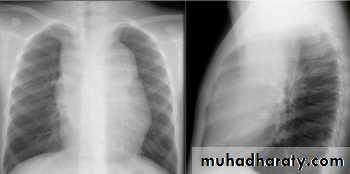

Hodgkin lymphoma

Posterior mediastinal mass